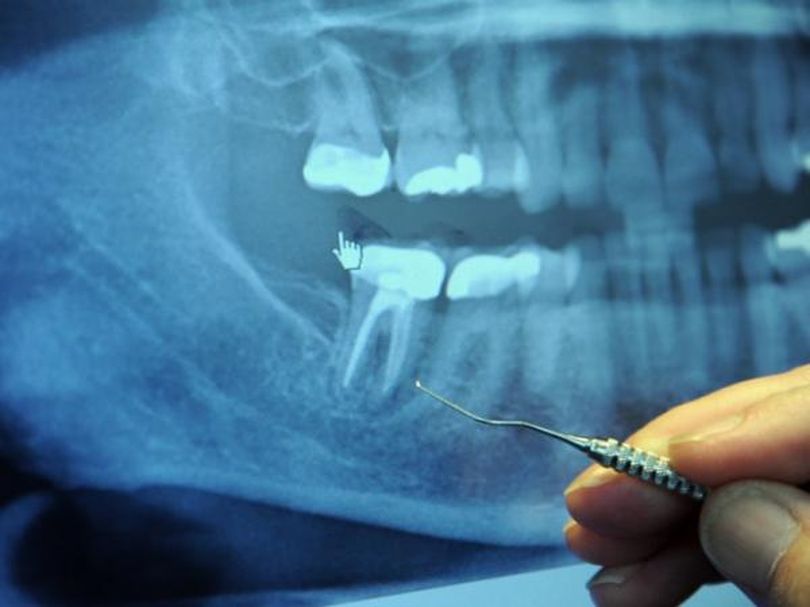

Корневой канал

В США ежегодно лечат 25 миллионов зубных корневых каналов.

Зубы, которые расположены в таких корневых каналах, являются «мертвыми» и могут накапливать токсичные анаэробные бактерии, которые, при определенных условиях, могут попасть в кровь и стать причиной ряда серьезных заболеваний, которые могут не проявлять себя в течение десятилетий.

Большинство таких токсичных зубов могут никак не болеть и выглядеть хорошо в течение многих лет, поэтому иногда очень сложно понять, какой именно зуб стал причиной болезни.

Когда дантист лечит корневой канал, он делает полость в зубе, затем заполняет дырку веществом, которое называется гуттаперча. Оно блокирует поставку крови в зуб. Исходя из этого, жидкость больше не способна циркулировать через зуб. Но лабиринт из крошечных туннелей остается. И бактерии, которые не получают питательных веществ, начинают прятаться в этих туннелях, где они находятся в полной безопасности от антибиотиков и от иммунной системы.

Никакое количество стерилизации не является эффективным, так как не может достичь этих каналов. В каждом таком зубе были найдены бактерии, особенно вокруг верхушки корня зуба и периодонтальной связки. Очень часто инфекция распространяется в челюсть, затем появляются дырки.